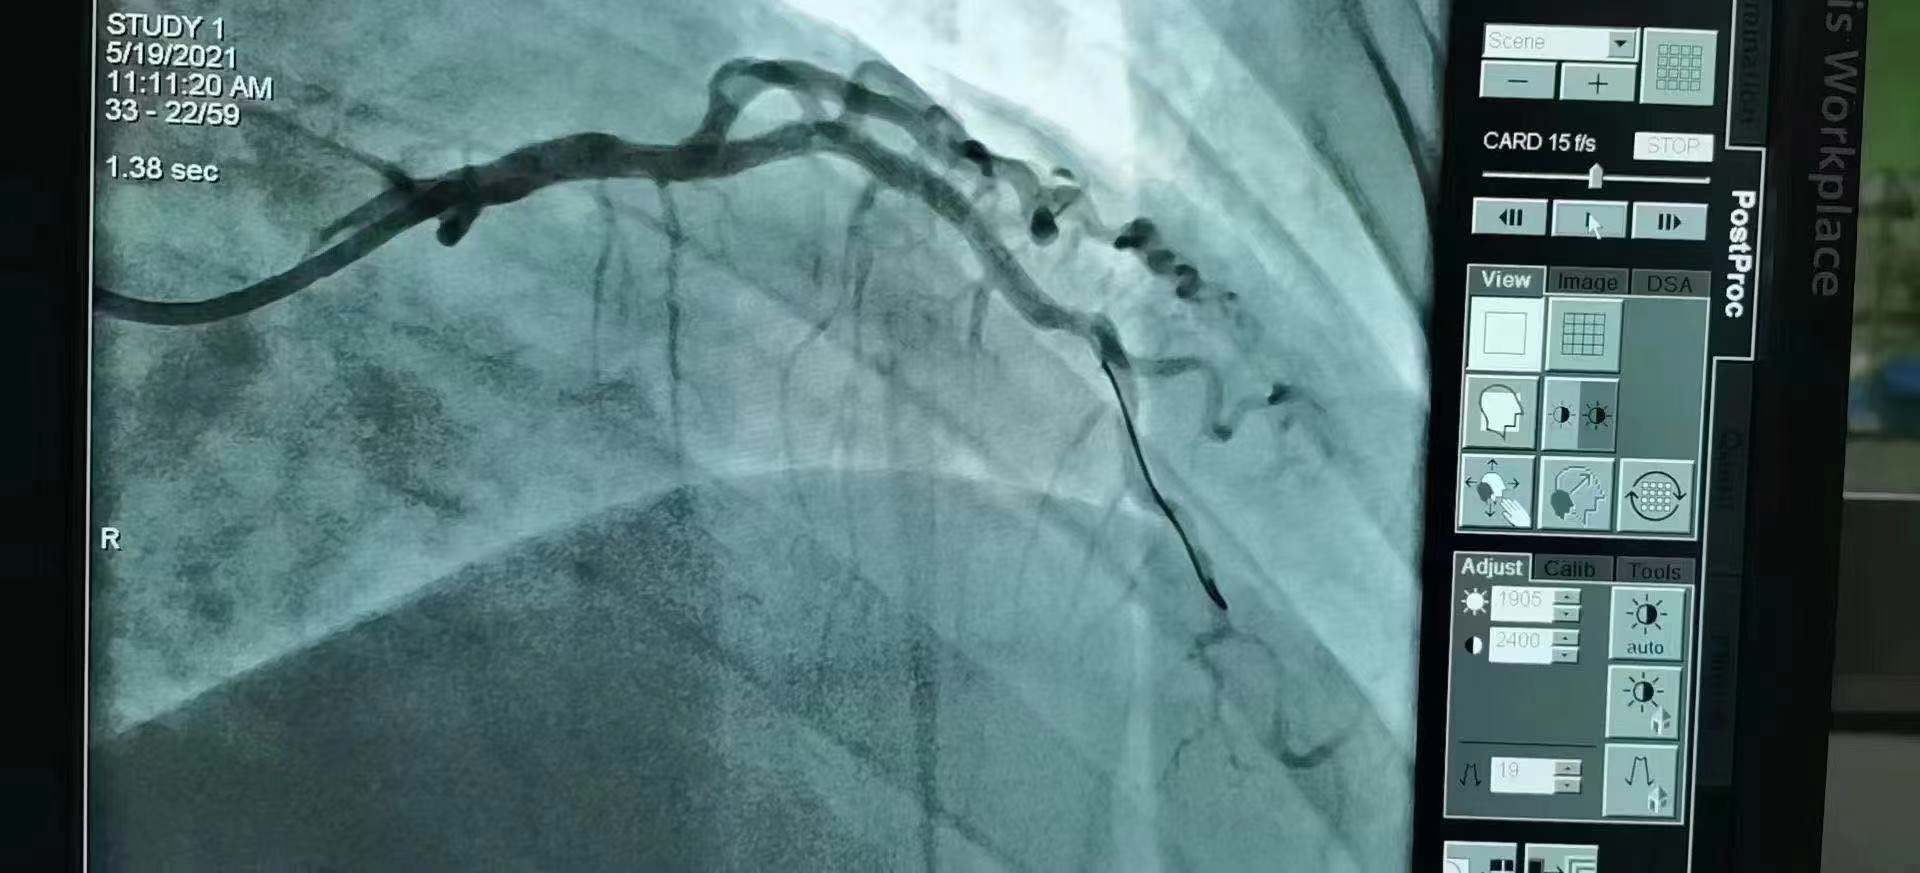

青島市第三人民醫院 李曉主任團隊成功為患者植入Xinsorb生物可吸收支架!

祝賀 青島市第三人民醫院  李曉主任團隊成功為患者植入Xinsorb生物可吸收支架!